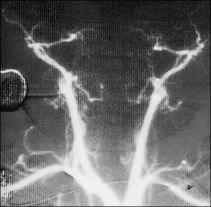

Con la introducción de la resonancia magnética (RM) en la práctica clínica se vio que era posible evaluar el flujo sanguíneo, tanto con las secuencias spin-eco como, especialmente, con las secuencias que son sensibles al flujo sanguíneo eco-gradiente. Utilizando este tipo de secuencias de pulso es posible la reconstrucción en tres dimensiones (3D) en forma de tiempo de vuelo (time of flight, TOF-3D) del árbol arterial cerebral y obtener una angiografía cerebral (fig. 6). Las imágenes reconstruidas verificarían la existencia o no de flujo arterial y venoso intracraneal, con las mismas aplicaciones que la ACIA o la ACIV, pero sin someter al paciente a la invasividad de un cateterismo o una inyección de medio de contraste22,23.

Fig. 6. Angiografía por resonancia magnética cerebral normal obtenida con técnica TOF-3D en visión frontal.

Aunque la experiencia es todavía limitada, Ishii et al22 ya describen los hallazgos con ARM en cuatro pacientes con muerte encefálica sin identificar flujo en las arterias carótidas internas en su porción supraclinoidea.